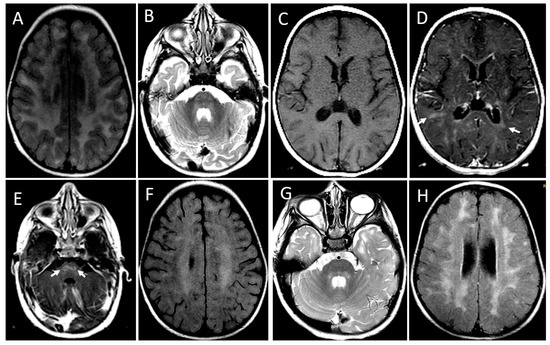

| Image Modality | Patient | 1 | 2 | 3 | 4 | 5 | 6 |

|---|---|---|---|---|---|---|---|

| Distribution | Diffuse/homogeneous | Patchy/asymmetric | Patchy/asymmetric | Patchy/asymmetric | Patchy/asymmetric | Patchy/asymmetric | |

| MRI at onset | Predominant location | Diffuse | Frontal and anterior temporal | Frontal and anterior temporal | Frontal and anterior temporal | Frontal and anterior temporal | Frontal and parietal |

| Infratentorial involvement | Pons | - | - | - | - | Pons | |

| Contrast enhancement | + | - | - | - | - | - | |

| MRI at follow up | Months after onset | 1st episode 8 mo (2 y 3 mo old) | |||||

| 2nd episode | |||||||

| 12 mo | 4 y | 10 mo | 24 mo | 13 y | 5 mo | ||

| (6 years old) | (6 years old) | (2 y 2 mo old) | (3 y 2 mo old) | (13 years old) | (20 mo old) | ||

| WM lesions improvement | Marked | Marked | Marked | Marked | Marked | Marked | |

| Brain Atrophy | Mild | - | Mild | - | - | - | |

| CT scan | Time after onset | 5 y | 4 y | 7 y | 1 mo | 13 y | 2 mo |

| Calcification | - | - | - | Basal ganglia | - | - |